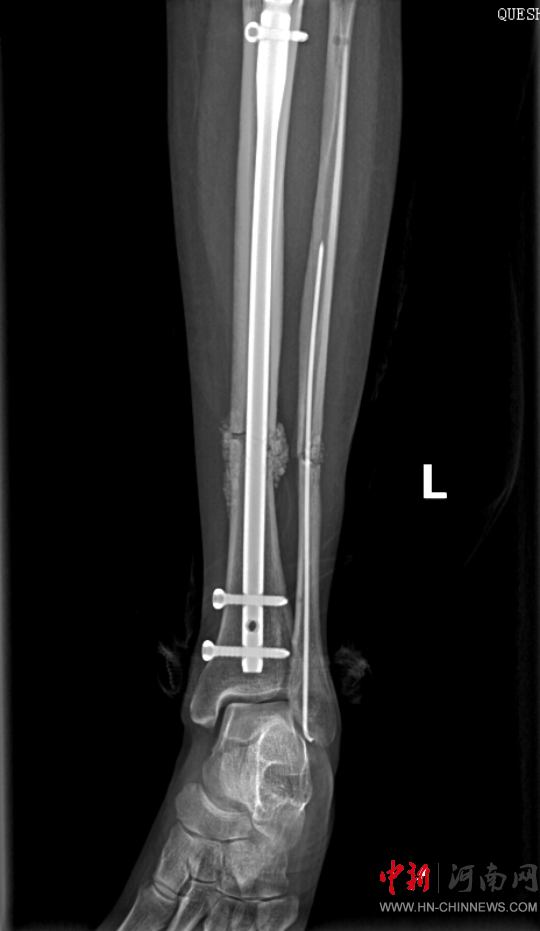

患者病情好轉(zhuǎn)后,該院急診科主任岳春彥和創(chuàng)傷治療團(tuán)隊(duì)為患者制定了詳細(xì)的手術(shù)規(guī)劃,傷后第10日,患者在全身麻醉下進(jìn)行“左股骨粉碎骨折及脛骨粉碎骨折髓內(nèi)釘內(nèi)固定術(shù)+骨移植術(shù)、腓骨骨折復(fù)位內(nèi)固定術(shù)”,病情平穩(wěn)后轉(zhuǎn)入急診科病房治療,切口愈合后,患者轉(zhuǎn)入康復(fù)醫(yī)學(xué)科進(jìn)行腦功能康復(fù)和下肢關(guān)節(jié)康復(fù)治療。目前,患者能夠與人正常溝通交流,左下肢關(guān)節(jié)功能也恢復(fù)良好,已出院。